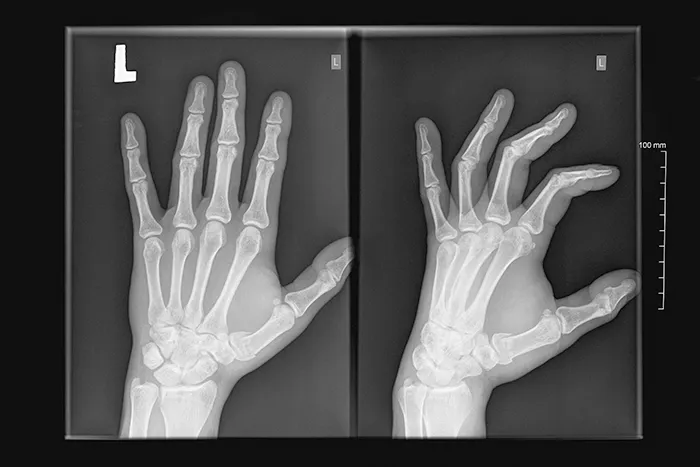

방송 등에서 방영된 류마티스 관절염의 경우에는 대부분 심각한 변형으로 손가락 관절이 변형되고 관절이 파괴된 사례가 많습니다. 이 유형의 경우에는 손가락뿐만이 아니라 어깨, 무릎등의 큰 관절에도 문제가 발생하여 인공관절 같은 수술과 치료를 받은 경우에 속한다고 볼 수 있습니다.

🔹증상: 손가락 마디가 커지고 굽힘 변형이 발생합니다.

류마티스 관절염은 면역체계의 이상으로 발생하며, 손뿐만 아니라 어깨나 무릎 등에도 영향을 미칠 수 있습니다.